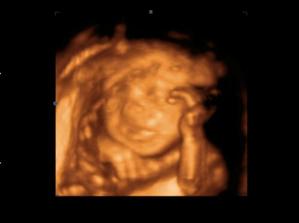

Jakubko

tak toto je náš Jakubko najkrajší vianočný darček

narodil sa 24.12.2007 o 4.10 ráno, vážil 4050 g a meral 51 cm